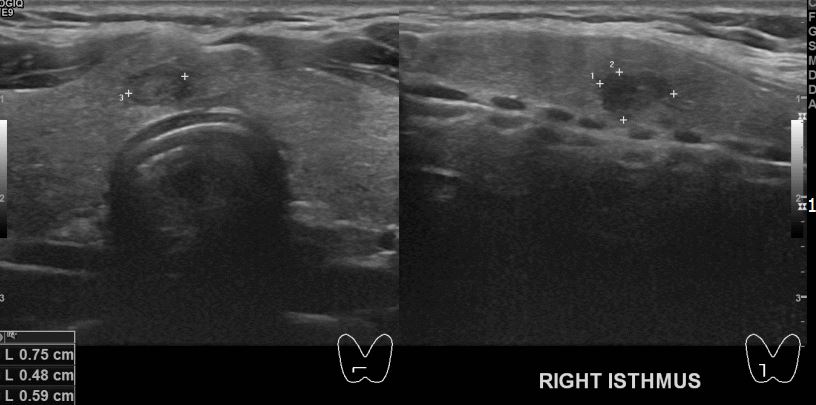

아산유외과 개원후 43번째 갑상선암 진단

건강검진상 이상 소견으로 내원하신 30대 남성분으로 의심스러운 혹 세침검사후

갑상선암 진단되셨읍니다.빠른 쾌유 바랍니다